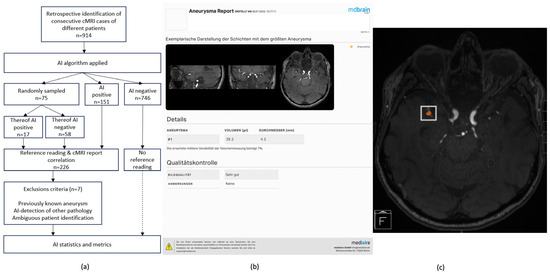

Worthwhile or Not? The Pain–Gain Ratio of Screening Routine cMRIs in a Maximum Care University Hospital for Incidental Intracranial Aneurysms Using Artificial Intelligence

by Franziska Mueller, Christina Carina Schmidt, Robert Stahl, Robert Forbrig, Thomas David Fischer, Christian Brem, Klaus Seelos, Hakan Isik, Jan Rudolph, Boj Friedrich Hoppe, Wolfgang G. Kunz, Niklas Thon, Jens Ricke, Michael Ingrisch, Sophia Stoecklein, Thomas Liebig and Johannes Rueckel

J. Clin. Med. 2025, 14(12), 4121; https://doi.org/10.3390/jcm14124121 - 11 Jun 2025

Background: Aneurysm-related subarachnoid hemorrhage is a life-threatening form of stroke. While medical image acquisition for aneurysm screening is limited to high-risk patients, advances in artificial intelligence (AI)-based image analysis suggest that AI-driven routine screening of imaging studies acquired for other clinical reasons could [...] Read more.

Background: Aneurysm-related subarachnoid hemorrhage is a life-threatening form of stroke. While medical image acquisition for aneurysm screening is limited to high-risk patients, advances in artificial intelligence (AI)-based image analysis suggest that AI-driven routine screening of imaging studies acquired for other clinical reasons could be valuable. Methods: A representative cohort of 1761 routine cranial magnetic resonance imaging scans [cMRIs] (with time-of-flight angiographies) from patients without previously known intracranial aneurysms was established by combining 854 general radiology 1.5T and 907 neuroradiology 3.0T cMRIs. TOF-MRAs were analyzed with a commercial AI algorithm for aneurysm detection. Neuroradiology consultants re-assessed cMRIs with AI results, providing Likert-based confidence scores (0–3) and work-up recommendations for suspicious findings. Original cMRI reports from more than 90 radiologists and neuroradiologists were reviewed, and patients with new findings were contacted for consultations including follow-up imaging (cMRI / catheter angiography [DSA]). Statistical analysis was conducted based on descriptive statistics, common diagnostic metrics, and the number needed to screen (NNS), defined as the number of cMRIs that must be analyzed with AI to achieve specific clinical endpoints. Results: Initial cMRI reporting by radiologists/neuroradiologists demonstrated a high risk of incidental aneurysm non-reporting (94.4% / 86.4%). A finding-based analysis revealed high AI algorithm sensitivities (100% [3T] / 94.1% [1.5T] for certain aneurysms of any size, well above 90% for any suspicious findings > 2 mm), associated with AI alerts triggered in 22% of cMRIs with PPVs of 7.5–25.2% (depending on the inclusion of inconclusive findings). The NNS to prompt further imaging work-/follow-up was 22, while the NNS to detect an aneurysm with a possible therapeutic impact was 221. Reference readings and patient consultations suggest that routine AI-driven cMRI screening would lead to additional imaging for 4–5% of patients, with 0.45% to 0.74% found to have previously undetected aneurysms with possibly therapeutic implications. Conclusions: AI-based second-reader screening substantially reduces incidental aneurysm non-reporting but may disproportionally increase follow-/work-up imaging demands also for minor or inconclusive findings with associated patient concern. Future research should focus on (subgroup-specific) AI optimization and cost-effectiveness analyses. Full article

Evaluation of AI-Powered Routine Screening of Clinically Acquired cMRIs for Incidental Intracranial Aneurysms

by Christina Carina Schmidt, Robert Stahl, Franziska Mueller, Thomas David Fischer, Robert Forbrig, Christian Brem, Hakan Isik, Klaus Seelos, Niklas Thon, Sophia Stoecklein, Thomas Liebig and Johannes Rueckel

Diagnostics 2025, 15(3), 254; https://doi.org/10.3390/diagnostics15030254 - 22 Jan 2025

Objectives: To quantify the clinical value of integrating a commercially available artificial intelligence (AI) algorithm for intracranial aneurysm detection in a screening setting that utilizes cranial magnetic resonance imaging (cMRI) scans acquired primarily for other clinical purposes. Methods: A total of [...] Read more.

Objectives: To quantify the clinical value of integrating a commercially available artificial intelligence (AI) algorithm for intracranial aneurysm detection in a screening setting that utilizes cranial magnetic resonance imaging (cMRI) scans acquired primarily for other clinical purposes. Methods: A total of 907 consecutive cMRI datasets, including time-of-flight-angiography (TOF-MRA), were retrospectively identified from patients unaware of intracranial aneurysms. cMRIs were analyzed by a commercial AI algorithm and reassessed by consultant-level neuroradiologists, who provided confidence scores and workup recommendations for suspicious findings. Patients with newly identified findings (relative to initial cMRI reports) were contacted for on-site consultations, including cMRI follow-up or catheter angiography. The number needed to screen (NNS) was defined as the cMRI quantity that must undergo AI screening to achieve various clinical endpoints. Results: The algorithm demonstrates high sensitivities (100% for findings >4 mm in diameter), a 17.8% MRA alert rate and positive predictive values of 11.5–43.8% (depending on whether inconclusive findings are considered or not). Initial cMRI reports missed 50 out of 59 suspicious findings, including 13 certain intradural aneurysms. The NNS for additionally identifying highly suspicious and therapeutically relevant (unruptured intracranial aneurysm treatment scores balanced or in favor of treatment) findings was 152. The NNS for recommending additional follow-/workup imaging (cMRI or catheter angiography) was 26, suggesting an additional up to 4% increase in imaging procedures resulting from a preceding AI screening. Conclusions: AI-powered routine screening of cMRIs clearly lowers the high risk of incidental aneurysm non-reporting but results in a substantial burden of additional imaging follow-up for minor or inconclusive findings. Full article